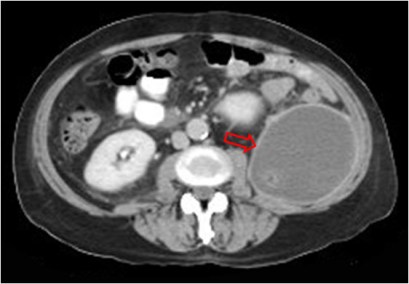

SIGNO DE LA CORTEZA o CÁSCARA

En la TC con contraste intravenoso, la pared de los abscesos en cualquier localización se realza de manera precoz, intensa y mantenida (flecha), mientras que el contenido no se realza. En la imagen, absceso en la fosa renal izquierda como complicación de una nefrectomía.